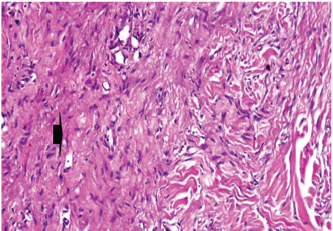

At 7 days post wounding; the inflammatory reaction was moderate and characterized by polymorphonuclear cells and macrophages infiltration with the presence of small scab covering the wound surface. Early evidence of epithelization was detected and represented by the proliferation of epidermal epithelium under the scab. There was marked thickening and hyperplastic proliferation of epidermal epithelium at the free wound edge (Fig. 6). The dermal tissue underlying the wound area showed few polymorphonuclear cells infiltration and more abundant mononuclear cells. Fibroplasia and angiogenesis were detected in the dermis and more extensive in deeper areas of the dermis which characterized by fibroblast and angioblast proliferation forming immature young granulation tissue (Fig. 7). At 14 days post wounding, the wound area was covered by a complete layer of epidermal epithelium indicating a good epithelization rate of the wound. Proliferation of cutaneous appendages was detected. The newly formed epithelium was thick and showed partial keratinization and epithelial differentiated stratum containing polyhedral keratinocyte with the appearance of keratohyalin granules in their cytoplasm (Fig. 8). The dermal tissue showed deposition of parallel well organized and interconnected collagen bundles that arranged parallel to epidermis associated with enhanced angiogenesis represented by well-developed blood capillaries (Fig. 9). At 21 days post wounding, remodeling of the formed epithelium with relatively small scar formation and mild restoration of skin appendages. Keratinized and differentiated stratum comprising the covering epithelium and the newly formed skin appendages from the basal epidermal epithelium were detected (Fig. 10). The dermal tissue revealed well-formed organized tissue consisted of parallel compact and interconnected bundles of collagen with scant angiogenesis (Fig. 11). At 28 days post wounding, well-formed scar tissue covering highly cellular organized tissue was detected (Fig. 12). The dermal tissue revealed well-arranged compact collagen bundles containing scarce blood vessels (Fig. 13).

Fig. 9. Skin of a goat from electroacupuncture group at 14 days post wounding showing well organized and interconnected collagen bundles that arranged parallel to each other and to epidermis (arrow head) associated with enhanced angiogenesis represented by well-developed blood capillaries (arrow), (HE ×200).

Fig. 10. Skin of a goat from electroacupuncture group at 21 days post wounding showing keratinized (arrow head) and differentiated stratum comprising the covering epithelium (*) and the newly formed skin appendages from the basal epidermal epithelium (HE ×200).